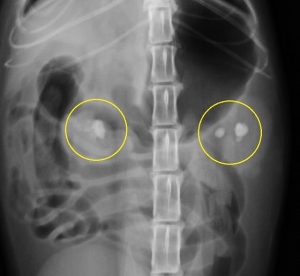

下の写真は両側の腎盂内に比較的大きな腎結石が発見された猫の腹部レントゲン写真です。上写真が縦方向下が横方向のものです。

猫でみられた腎結石のレントゲン写真を左下図に示します。その中で「白く見える3つの影」が腎臓(腎盂内)にある腎結石です。イメージしやすいように結石と腎臓の位置関係を右の模式図に重ねてみました。結石は実際には腎臓の腎盂内にあるので外からは見えません。一番左の結石は尿管に落ちかかっています。